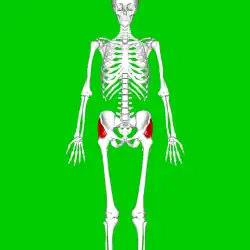

Hanche droite. Vue externe.

Hanche droite. Vue externe. Fémur droit. Vue postérieure.